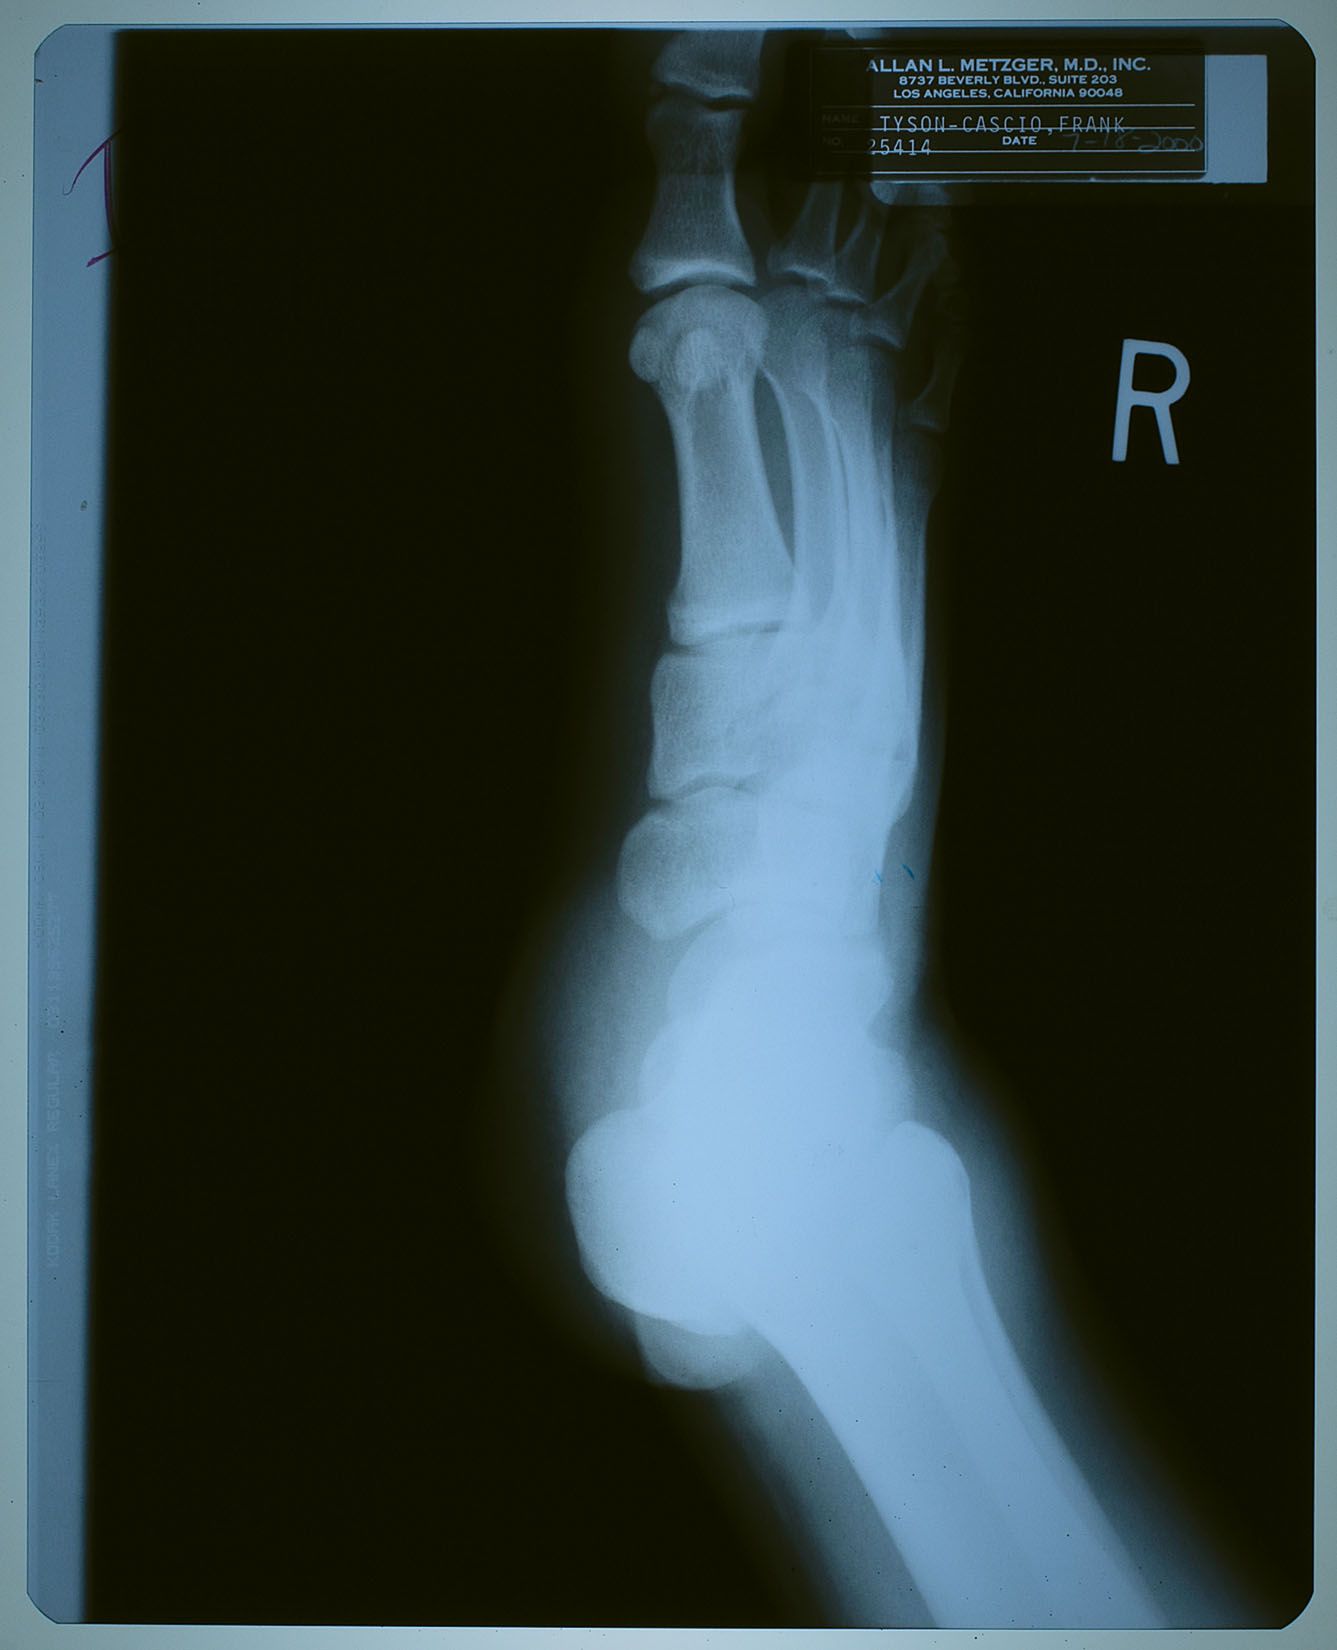

2000年7月18日、ネバーランドで子供たちと遊んでいて

怪我をした時に撮ったX線写真。

名前が 「タイソン-カシオ,フランク」 になっているけども、

カシオ本を読んだ御仁はお判りでしょう。

"タイソン" というのは、前年からマイケルの代理人を務めるようになった

フランク・カシオ君の仕事上での通名。

診療所などでは、マイケルがプライバシー面からフランク君の名を使う事もあったそう。